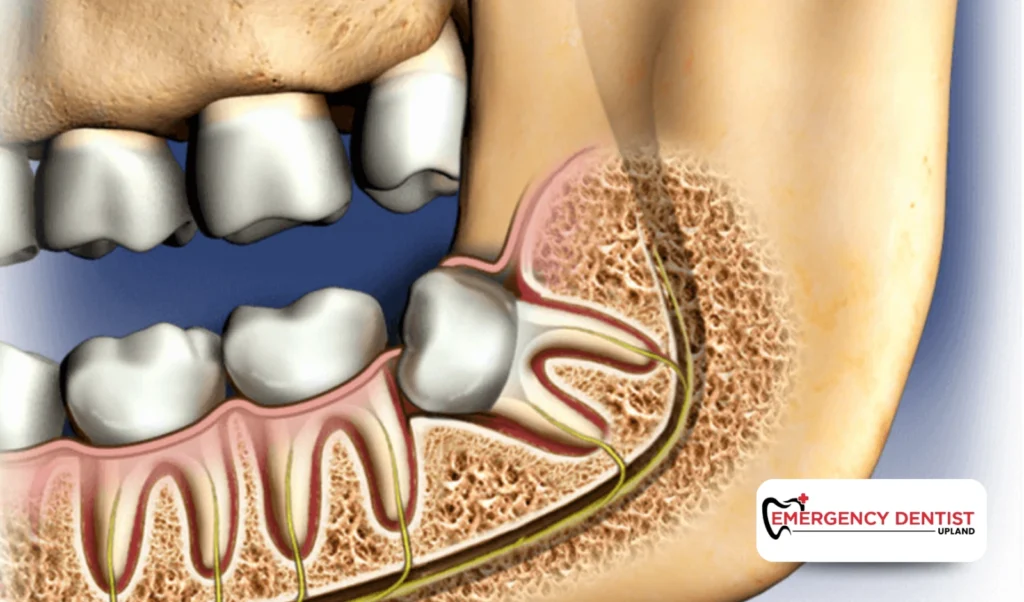

A surgical extraction is required when the tooth is impacted, broken, or positioned under the gums. This approach may involve lifting gum tissue or dividing the tooth, which can influence overall wisdom teeth removal cost.

Some wisdom teeth grow straight and are fully erupted, making them easier to remove. Others may be angled, partially visible, or trapped beneath the gums, which increases the complexity of the dental procedure.

An impacted wisdom tooth does not fully break through the gums. This can lead to pressure, swelling, infection, or damage to surrounding teeth.

Because impacted teeth often require more planning and surgical steps, they commonly affect the average cost of a wisdom tooth removal more than straightforward extractions.